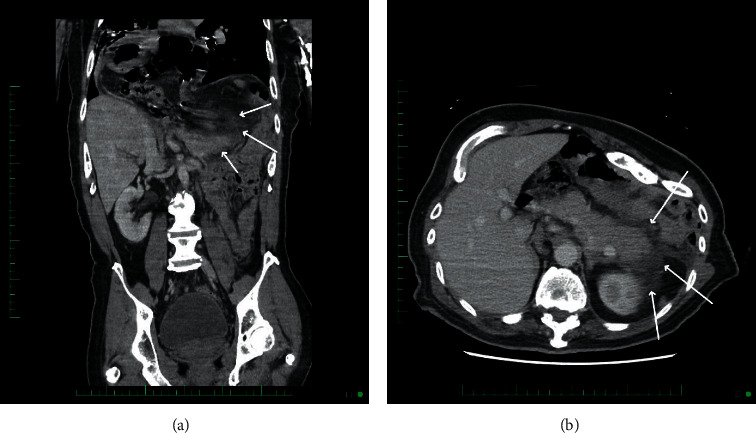

急性胰腺炎是一种常见的胃肠道原因在世界各地的住院治疗。急性胰腺炎最常见的病因包括胆结石、过度饮酒、高甘油三酯血症,或少数情况下的创伤。牵引性胰腺炎是一种罕见的急性胰腺炎,但以前有报道。我们报告一位60岁男性,既往有脑瘫病史,以先天性膈疝继发急性胰腺炎就诊。

Acute pancreatitis is a common gastrointestinal cause of hospitalizations across the world. The most common etiologies of acute pancreatitis include gallstones, excessive alcohol use, hypertriglyceridemia, or, rarely, trauma. Traction-induced pancreatitis is an uncommon but previously reported cause of acute pancreatitis. We present a 60-year-old male with a past medical history of cerebral palsy who presented to our facility with acute pancreatitis secondary to a congenital diaphragmatic hernia.